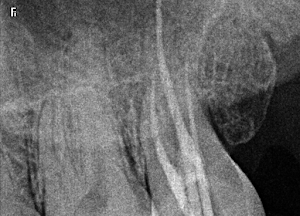

Welcome to our gallery

See how our company transforms ideas into reality. This gallery is a visual testament to our work and achievements.